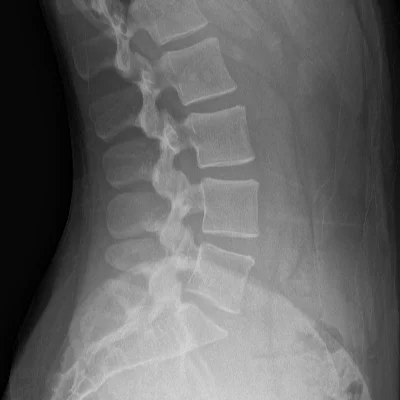

Spine X-Ray

Cervical, thoracic, and lumbar spine imaging for fractures, disc degeneration, and scoliosis.